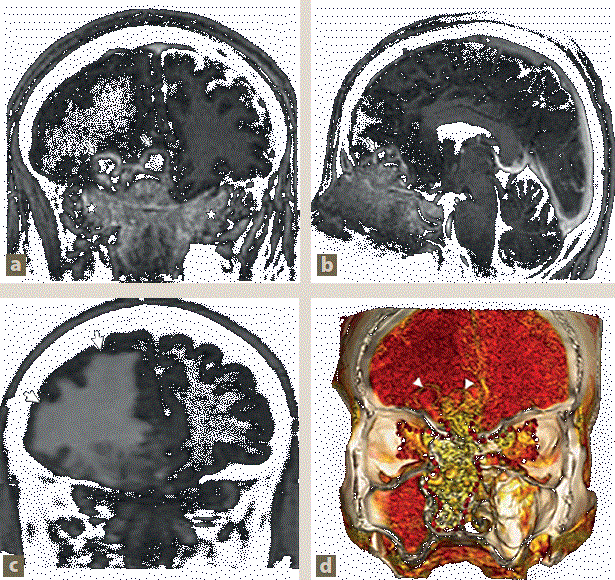

Imagen: Prado Hernández et al.

Figura 2 Tumor nasal con extensión intracraneal. a) y b) Resonancia magnética (RM) en T1 + Gd, cortes coronal y sagital, mostrando el tumor nasal con extensión intraorbitaria bilateral (asteriscos) y realce homogéneo intenso, así como extensión intracraneal en forma de imágenes quísticas con realce en anillo (flechas delgadas). c) RM en T2 FLAIR, corte coronal que evidencia un extenso edema vasogénico en el lóbulo frontal derecho (flechas gruesas). d) Reconstrucción 3D del tumor nasal, mostrando extensión intracraneal (cabeza de flecha) y a las fosas nasales (puntos rojos).

Figura 3 Tumor nasal con extensión intracraneal. a) Resonancia magnética (RM) en T2 axial, que muestra ocupación total de las celdillas etmoidales y senos esfenoidales con alta señal de aspecto heterogéneo (cabeza de flecha). b) RM T2 FLAIR axial, con ocupación total del seno maxilar derecho, que presenta alta señal (asteriscos). c) y d) Difusión y mapas de ADC del tumor nasal con extensión intraorbitaria bilateral (puntos) que muestran restricción a la difusión, secundaria alta proliferación celular.